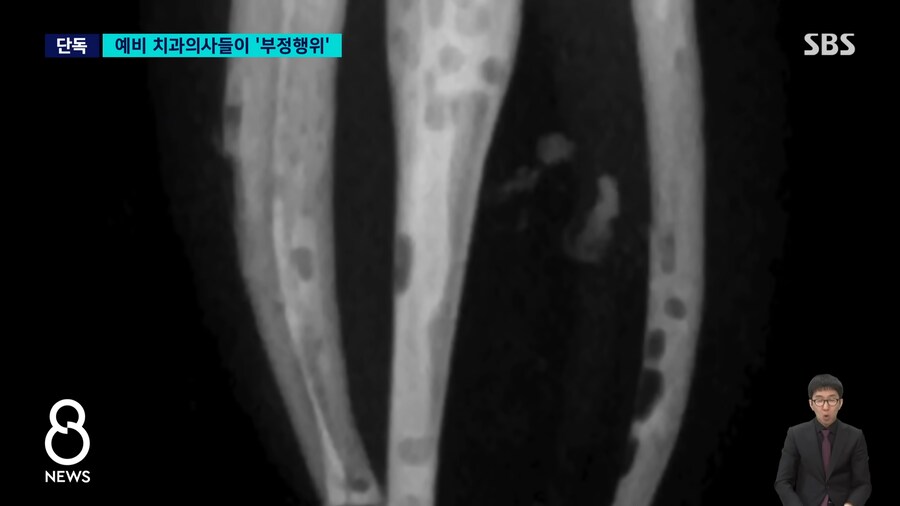

저기 구멍뚫린것 처럼 보이는 검은색이 신경치료하면서 충전제를

꼼꼼히 채워넣지 못한 부분..

교수에게 제출한 사진

포토샵등으로 검은 부분 메꿔서 제출...